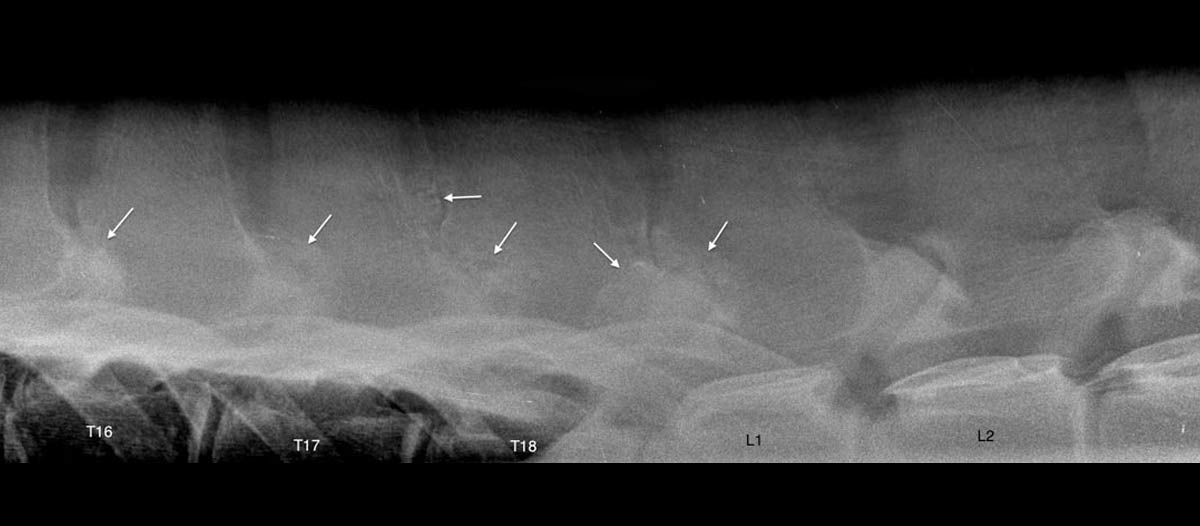

Radiology is an already long-lasting technique that is still a big evolution in this modern digital world. EquiSound features two digital radiography systems combined with a strong x-ray machine of 80.000 Watt (80 kV). We can make radiographs of excellent quality of the complete horse, including head, neck and back.